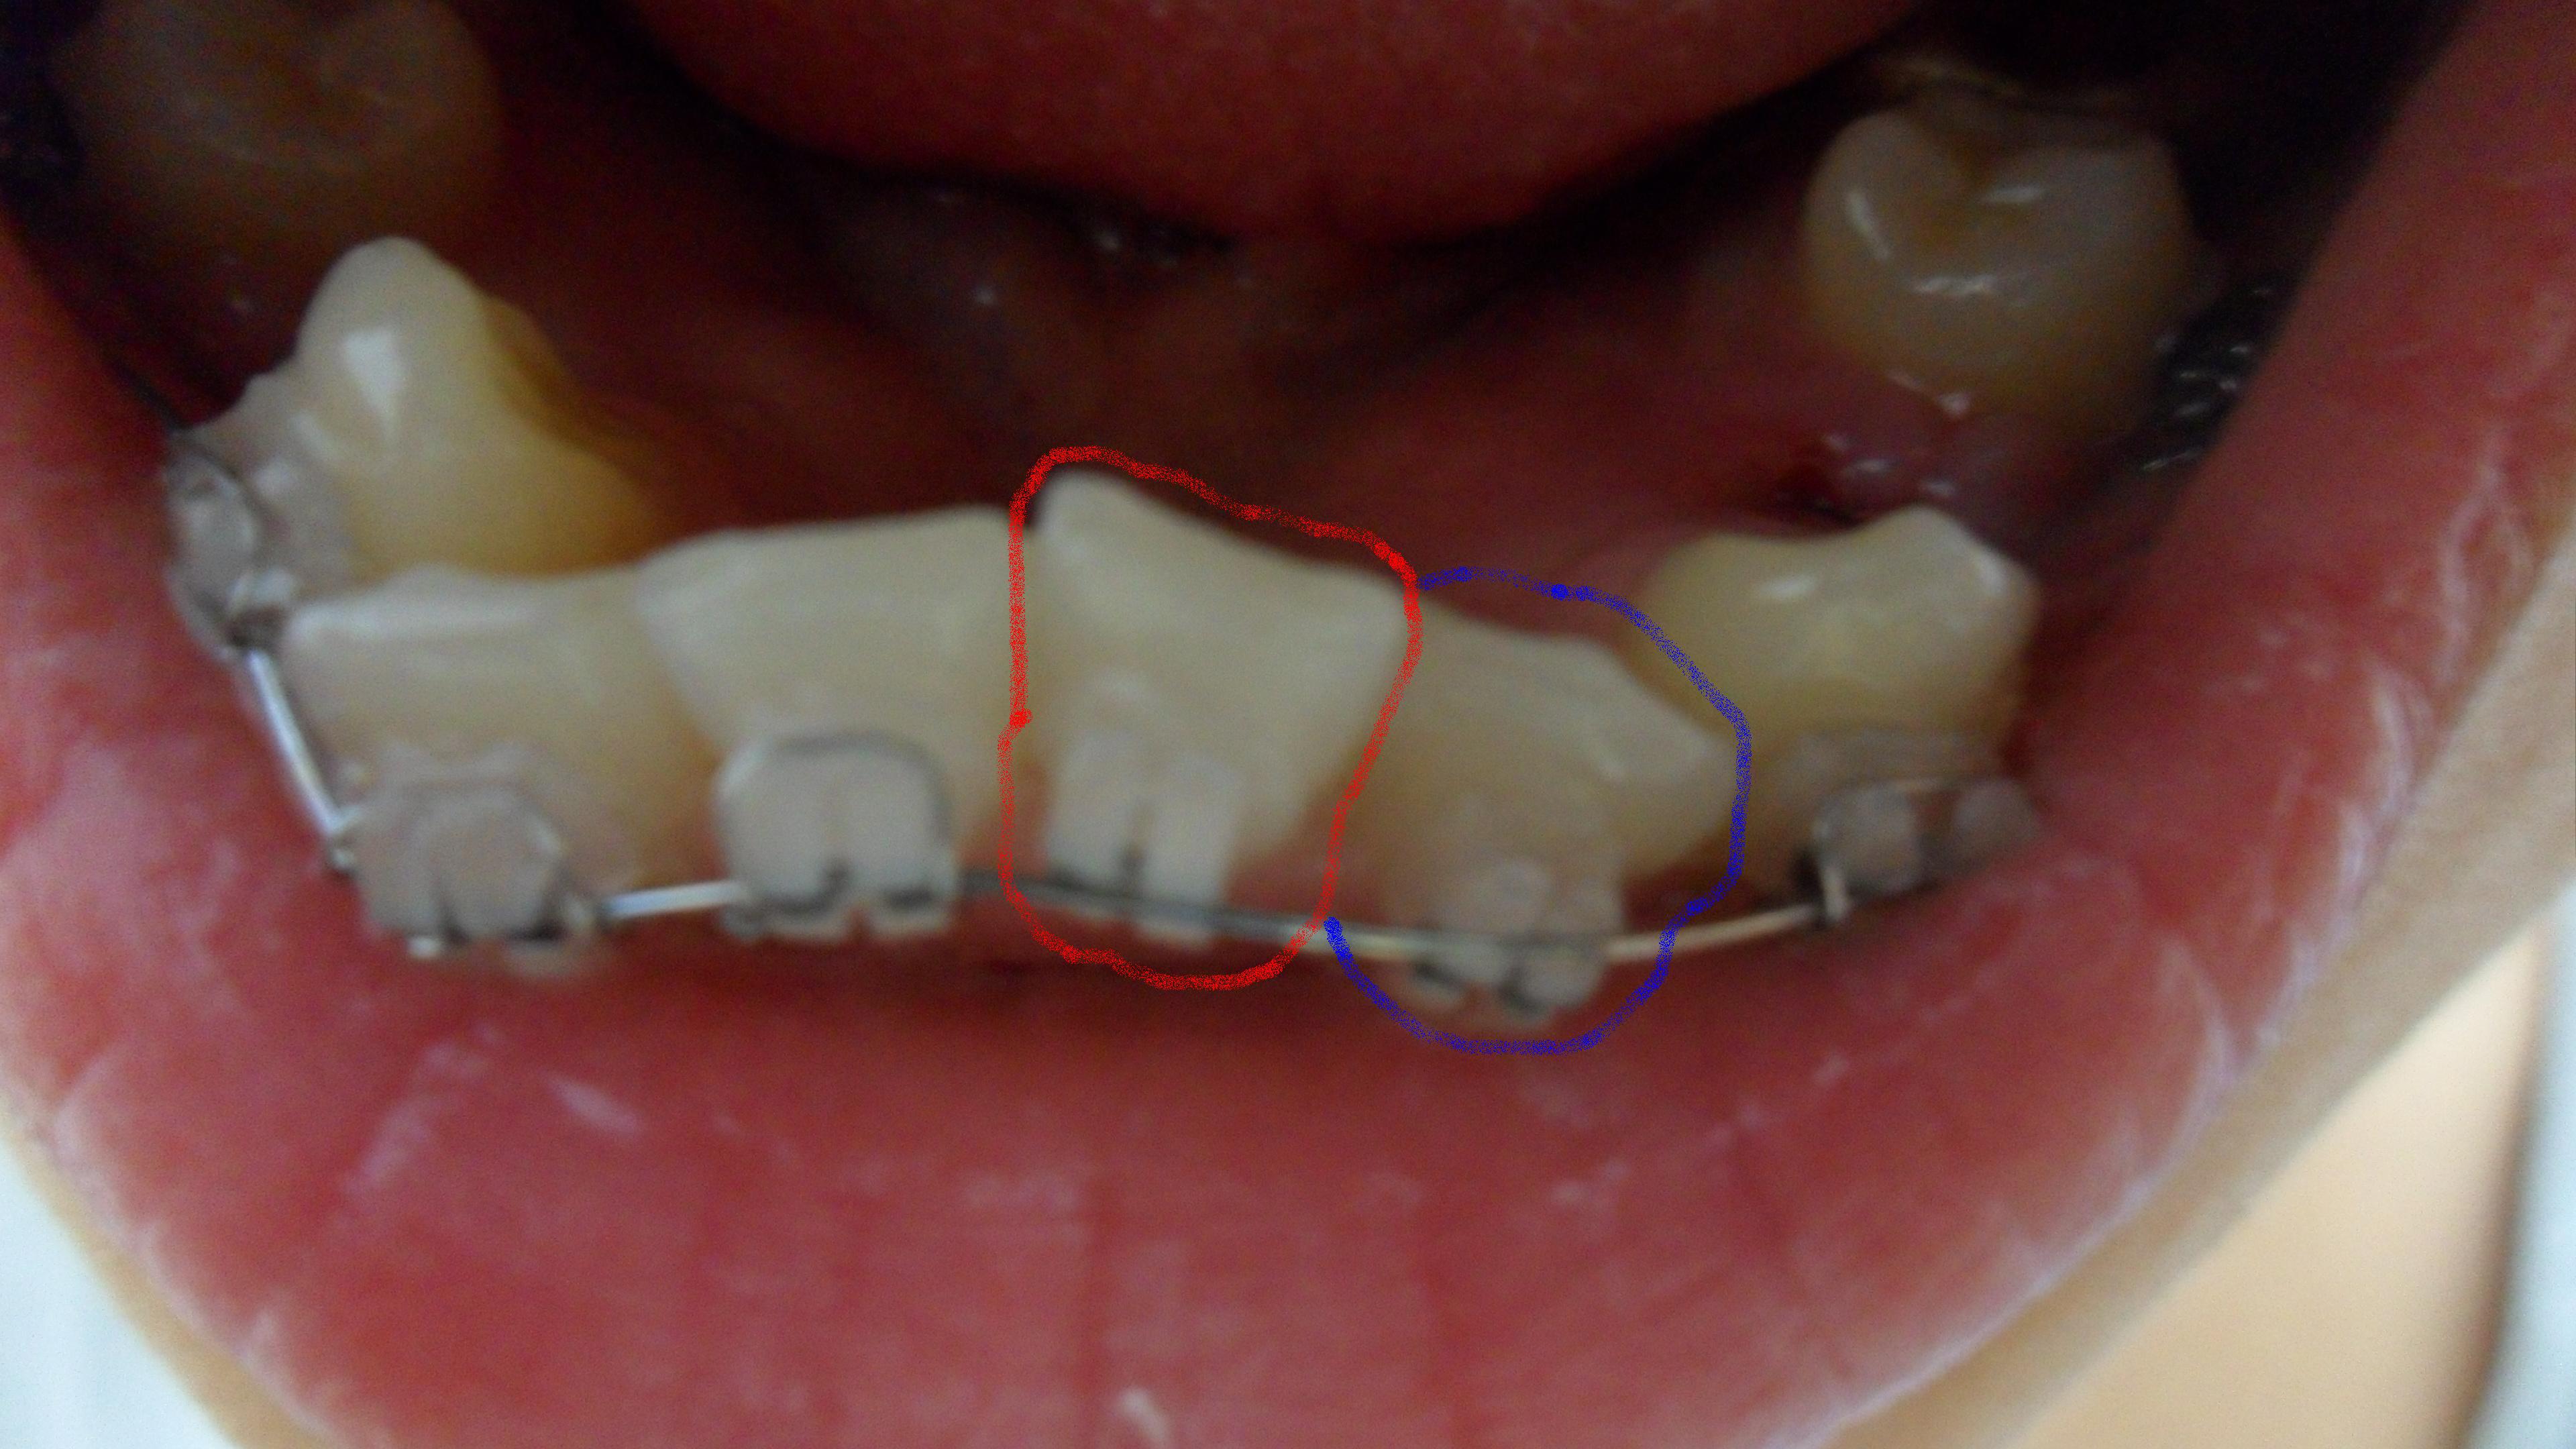

지금 교정시작한지 8개월정도 되었습니다. 제가봤을땐 별로 변한게 없는거같아서여~ 현재 윗니는 비발치상태이며 장치만 달아놓고 아직 아무것도 안해주고 계시구여(윗니도 발치 해야함.), 아랫니는 앞니 삐뚤어진거 ...